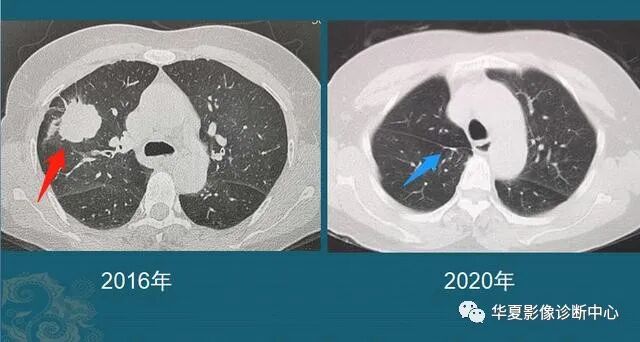

从1个小结节,发展成肺癌,需要几年?看看诊断实例...